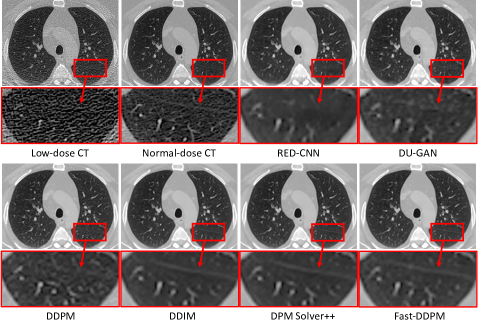

Refer to caption

Figure 5: Qualitative results of the CT image denoising task.

Figure 5 shows the low-dose, normal-dose, and predicted normal-dose CT images generated by various models for a representative subject. The zoomed-in region, highlighted by red rectangular boxes, demonstrates the ability of our Fast-DDPM model to preserve fine structural details in the denoised images compared to other methods. Notably, the lung fissure appears clearest and sharpest in the image produced by Fast-DDPM, while other methods (except for DDIM and DPM-Solver++) exhibit noticeable blurring and loss of detail in this region. A pulmonary fissure is the boundary between lobes of the lung. Preserving fissure details enables automated segmentation of the lung lobes, facilitating more detailed analysis of lung diseases at the lobar level.